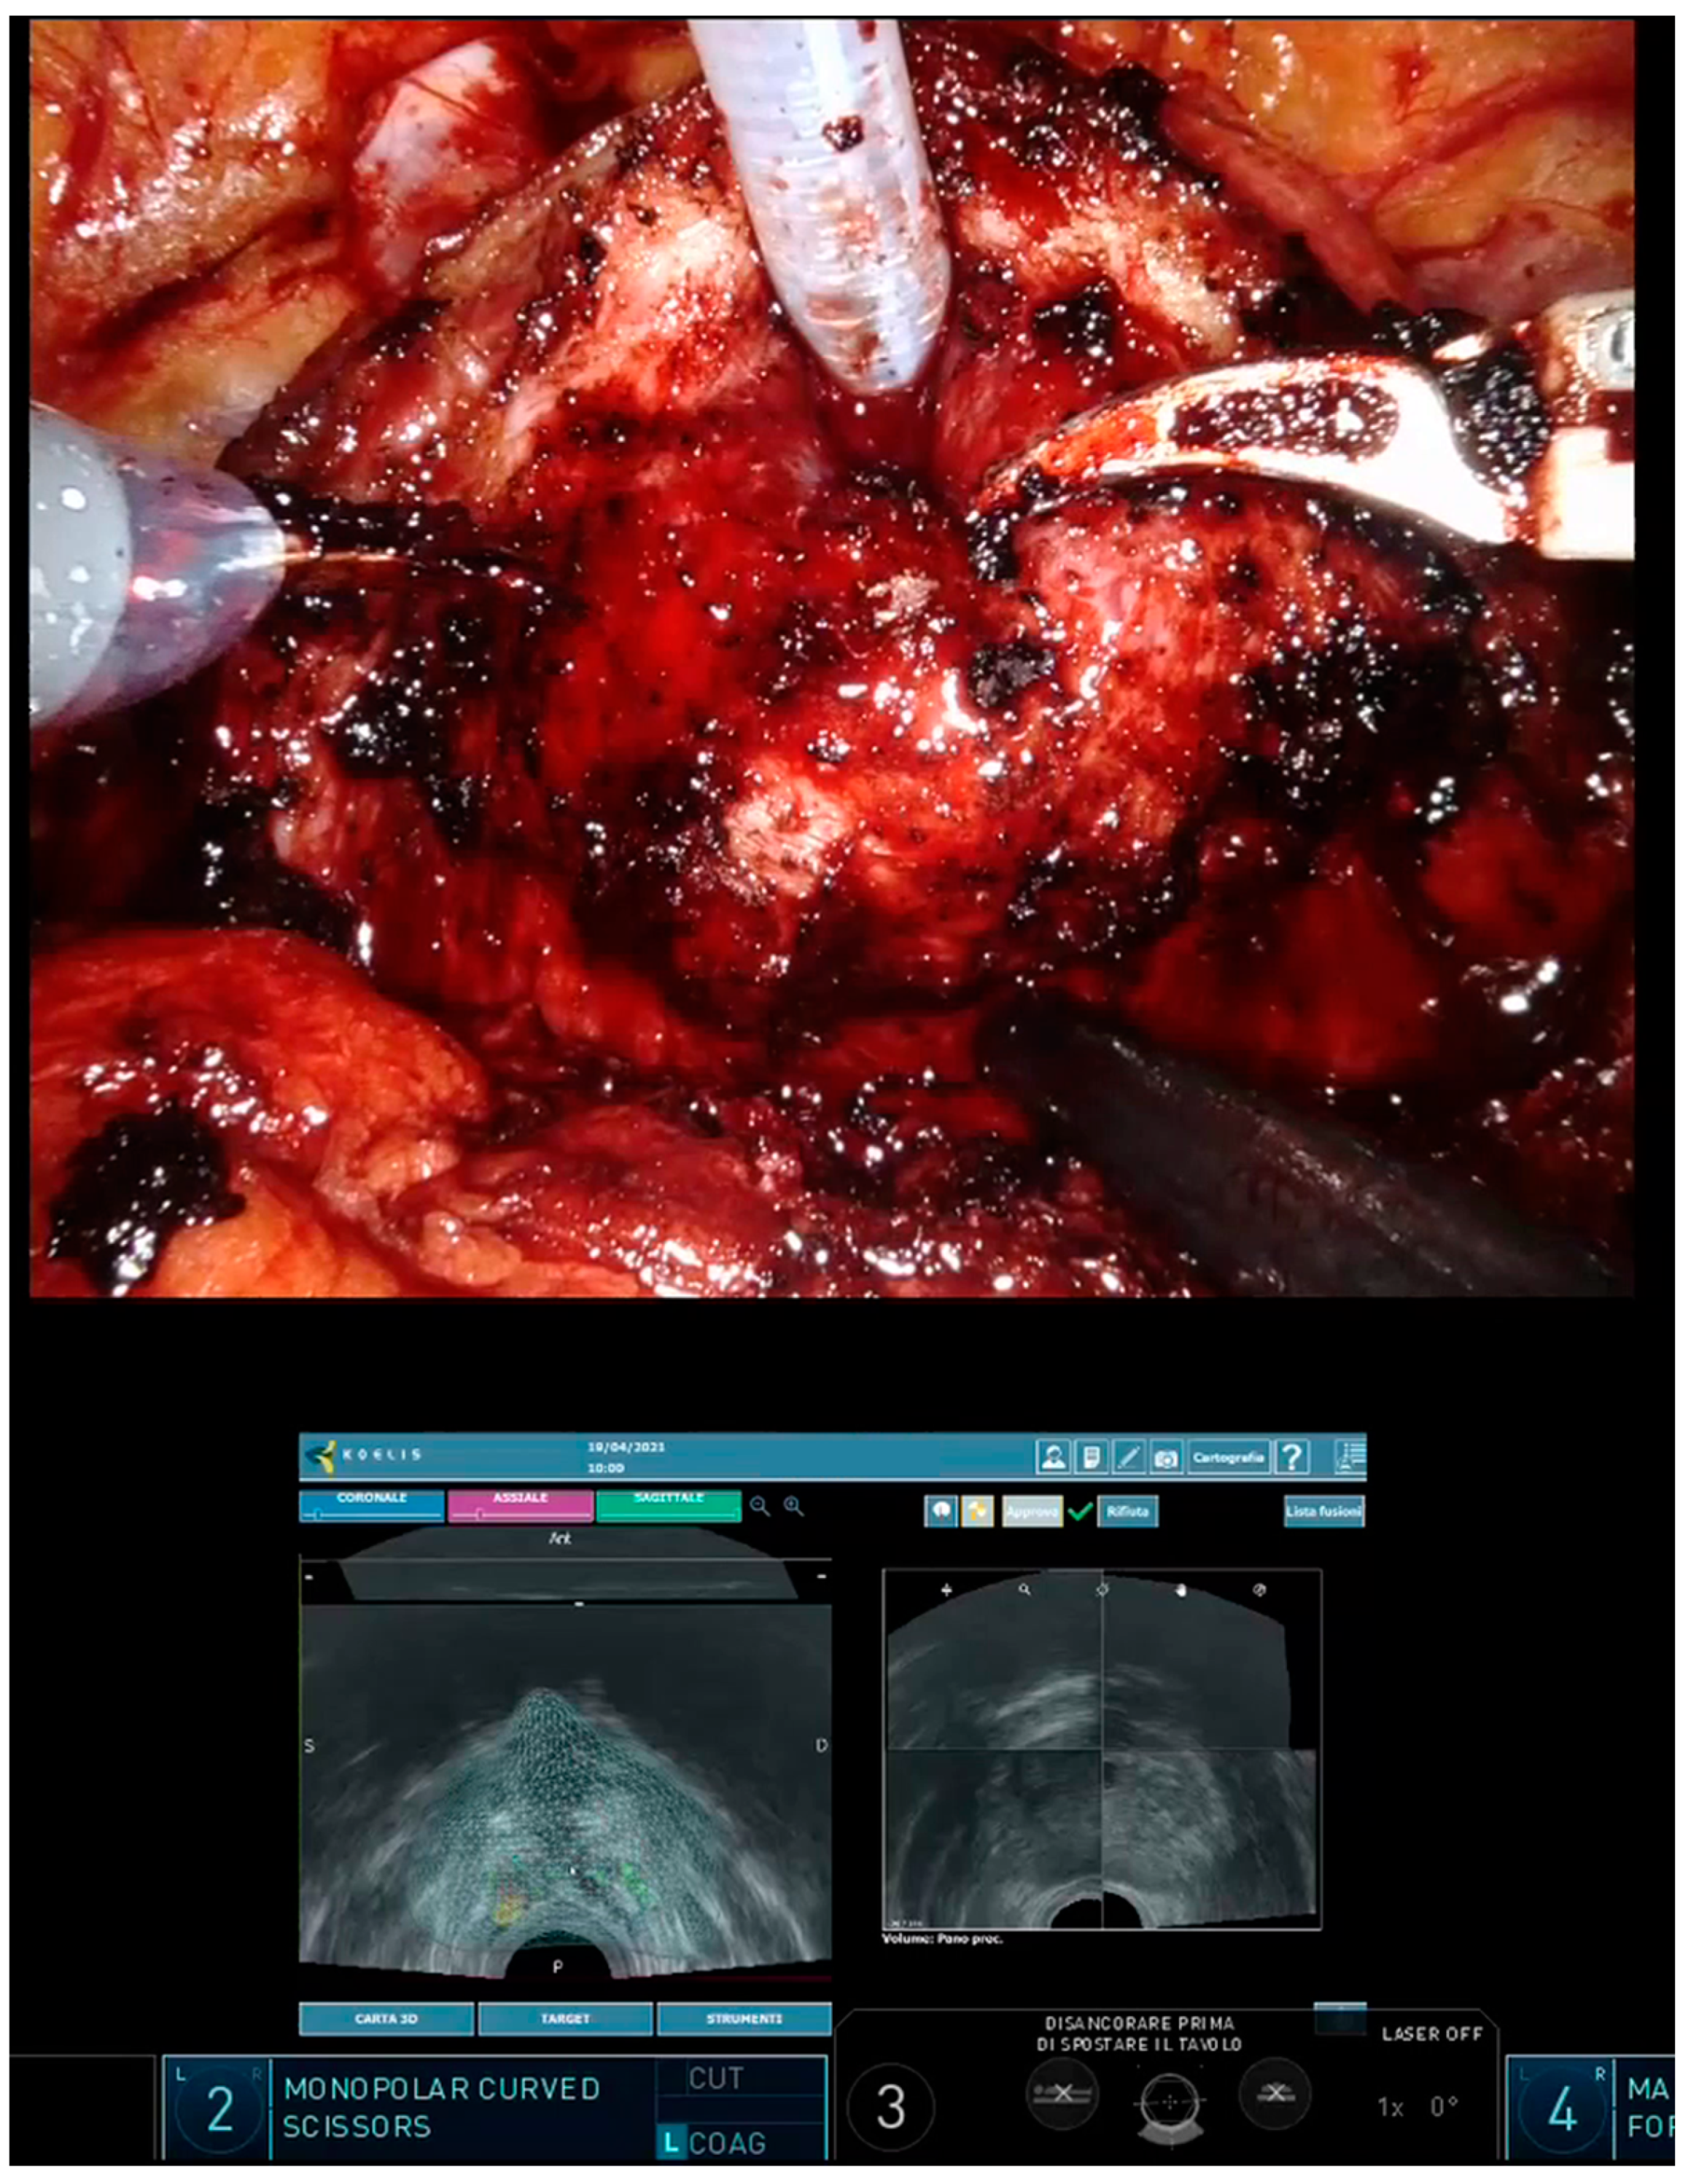

Intraoperative 3D-US-mpMRI Elastic Fusion Imaging-Guided Robotic Radical Prostatectomy: A Pilot Study

Oderda, M.; Calleris, G.; D’Agate, D.; Falcone, M.; Faletti, R.; Gatti, M.; Marra, G.; Marquis, A.; Gontero, P. Intraoperative 3D-US-mpMRI Elastic Fusion Imaging-Guided Robotic Radical Prostatectomy: A Pilot Study. Curr. Oncol. 2023, 30, 110-117. https://doi.org/10.3390/curroncol30010009